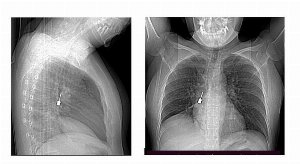

L’esame ha mostrato un corpo estraneo metallico bloccato nel bronco lobare inferiore del polmone destro. L’oggetto, risultato poi essere un cacciavite odontoiatrico, era accompagnato da un pneumomediastino, segnale di una condizione potenzialmente pericolosa.

Alla luce del quadro clinico, i medici hanno disposto il ricovero immediato e il trasferimento in sala operatoria. La priorità era rimuovere l’oggetto prima che potesse provocare infezioni, perforazioni o ulteriori danni respiratori.

L’estrazione è avvenuta tramite broncoscopia, una procedura mininvasiva ma complessa, eseguita dall’équipe di Chirurgia Toracica. L’intervento si è svolto senza imprevisti, consentendo di recuperare il cacciavite in modo sicuro.